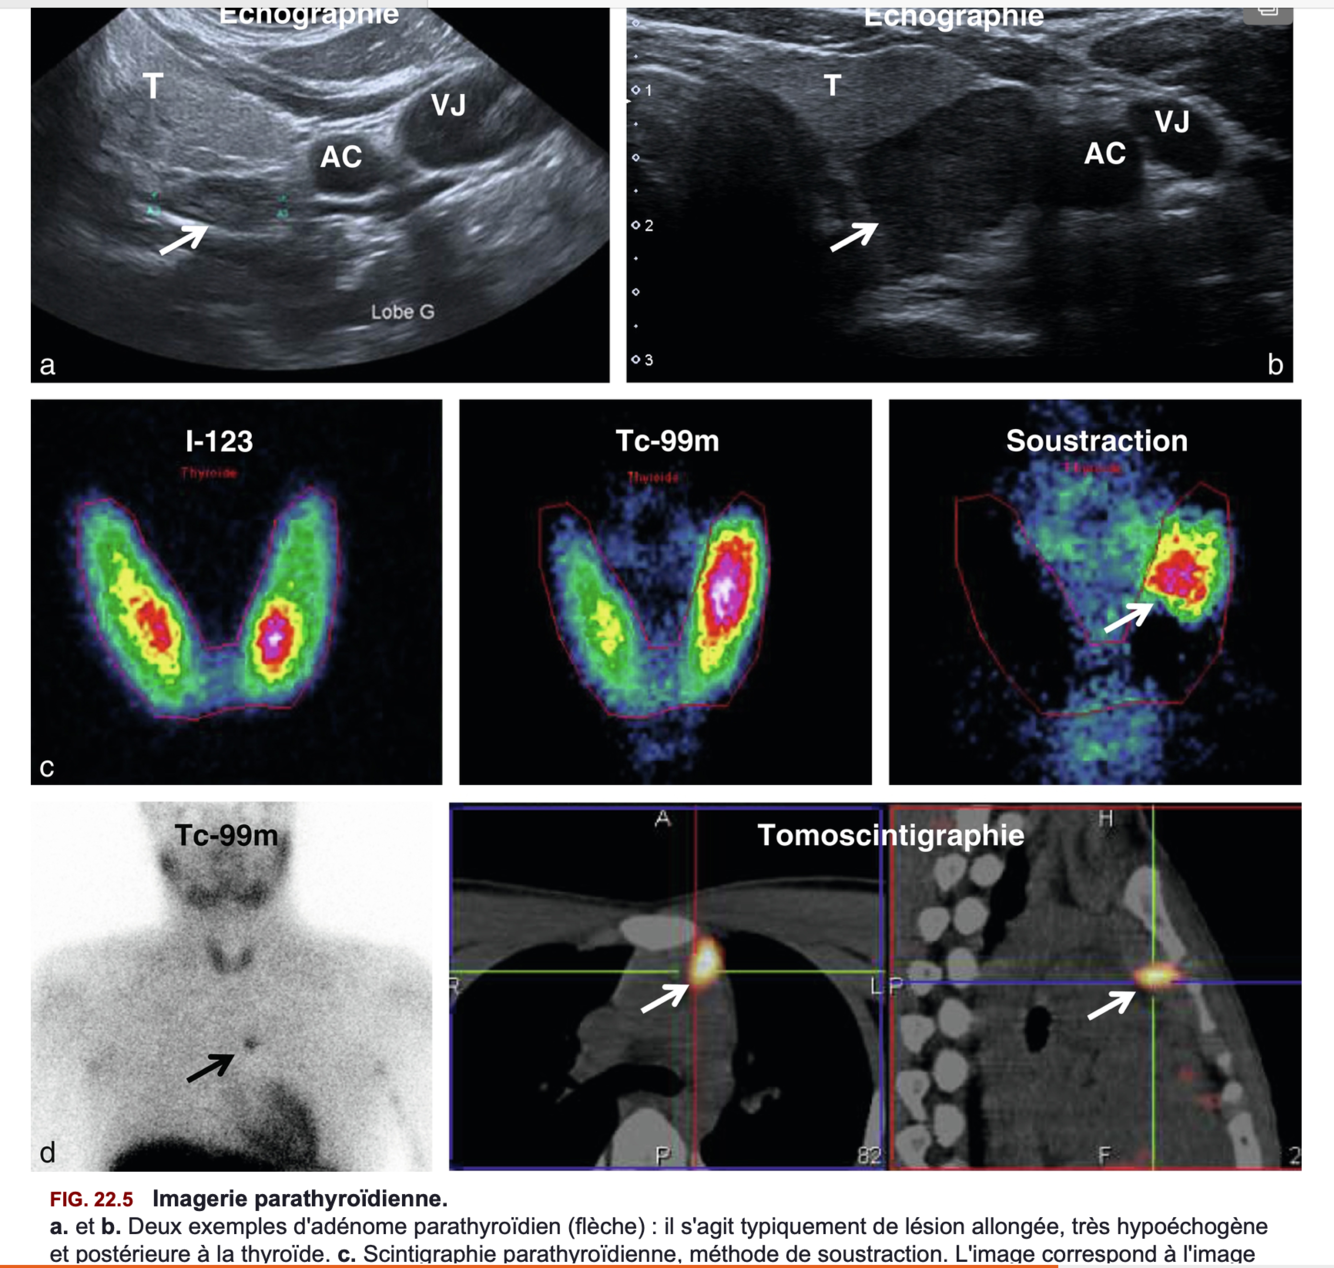

Imagerie utiles devant une hyperparathyroidie primaire =

=> figure 22.5

Indications de l’imagerie avant la chirurgie dans l’hyperparathyroidie primaire =